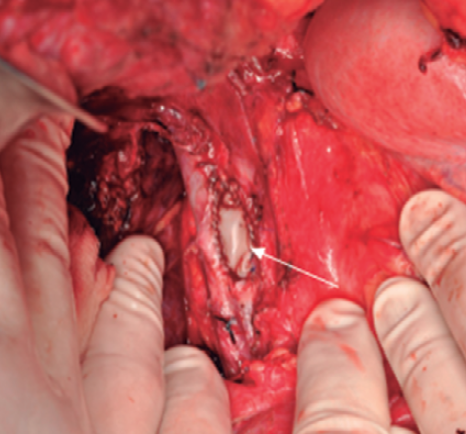

Guillermo Rencoret Palma, Marcelo Vivanco Lacalle, Felipe Andrés Castillo Henriquez, Giancarlo Schippacasse, Xabier De Aretxabala Urquiza, Victor Bianchi, Juan Hepp, Horacio Rios